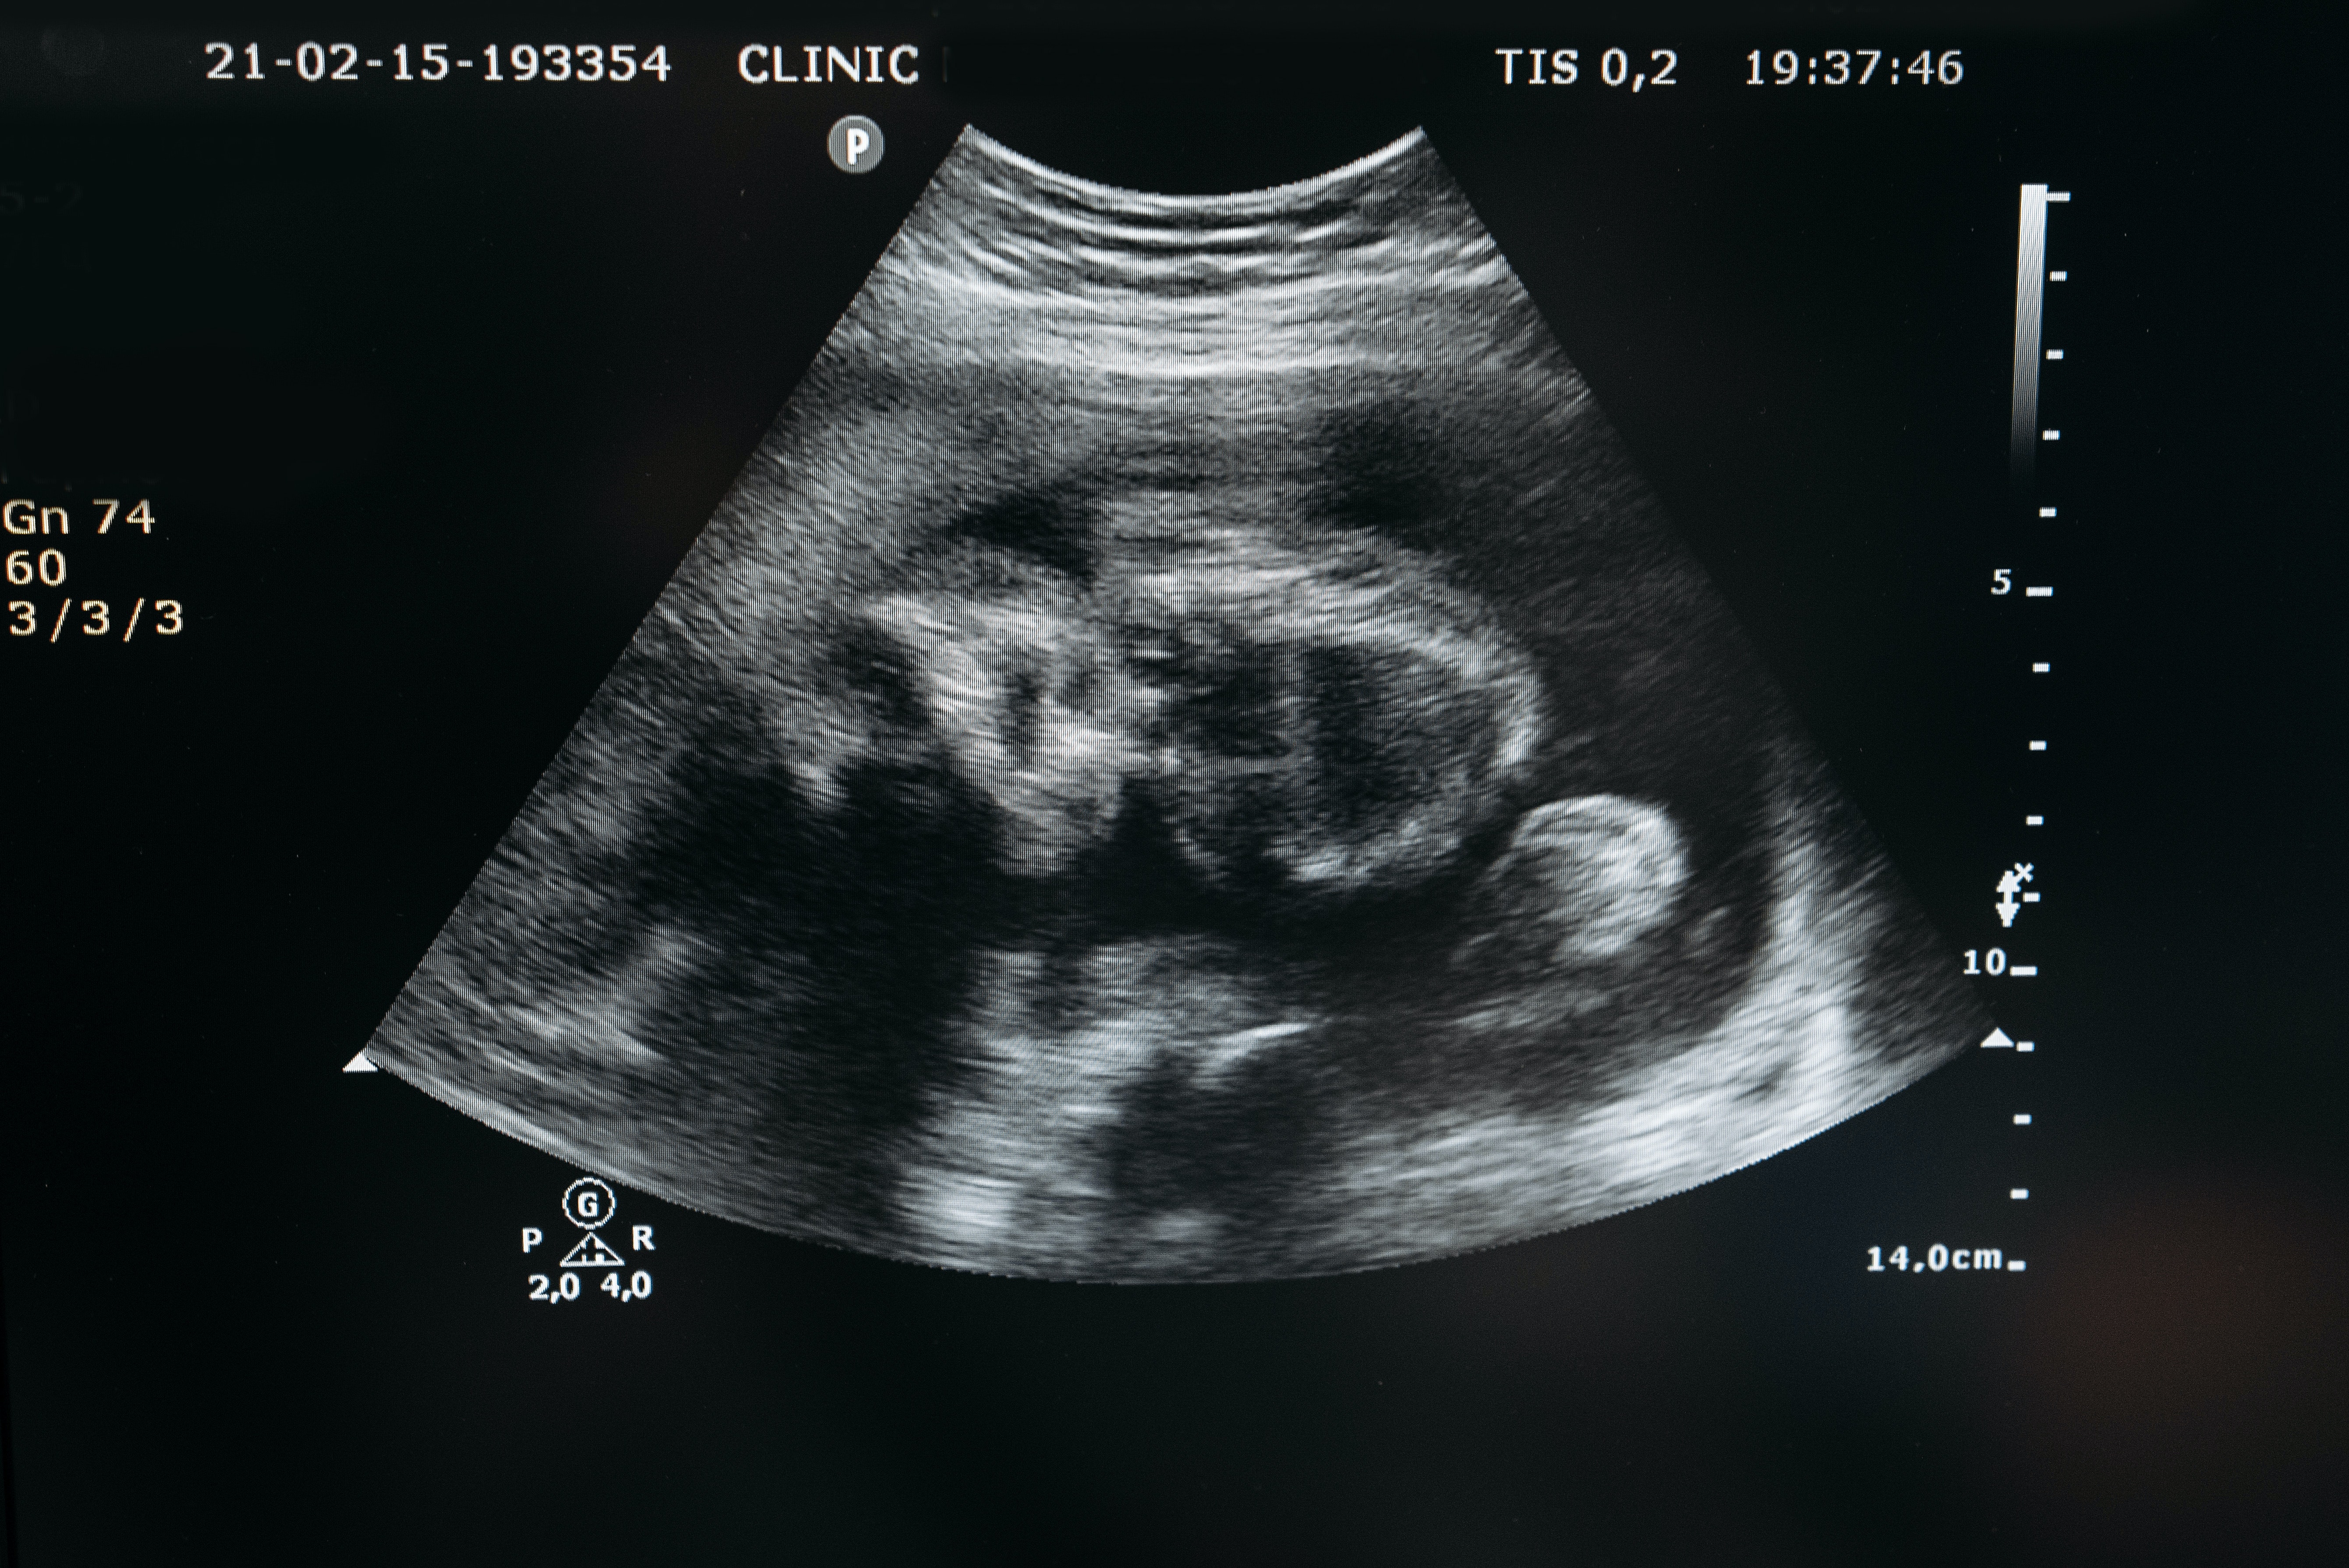

Kjo pajisje nuk është një kopje fantastiko-shkencore e mitrës njerëzore që nga ngjizja deri në lindje. Studiuesit e CHOP shpresojnë të imitojnë disa elementë të një mitre natyrale për të rritur shkallën e mbijetesës dhe rezultatet shëndetësore të foshnjave jashtëzakonisht të parakohshme, ato të lindura para javës së 28-të të shtatzënisë.

EXTEND funksionon duke vendosur foshnjat e lindura para kohe në një “Biobag” të mbushur me një lëng të veçantë që imiton lëngun amniotik. Enët e gjakut të foshnjës në kordonin e kërthizës janë të lidhura me një sistem të jashtëm i cili oksigjenon gjakun, duke simuluar rolin e placentës.